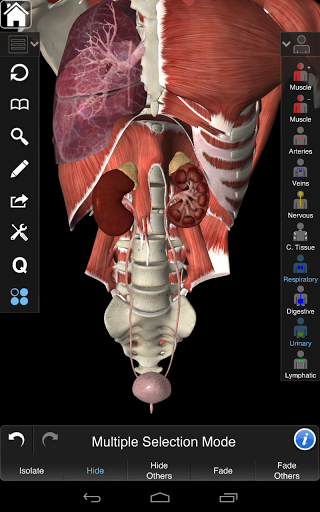

Ta aplikacja zawiera niezbędną anatomię dla 10 systemów:

⁃Szkieletowy

⁃Muscles

⁃Tkanka łączna

⁃Żyły

⁃Artyki

⁃Nerwowość

⁃Oddechowy

⁃Trawienny

⁃Moczowy

⁃Limfatyczny

Zawiera także mózg i serce

Essential Anatomy 3 jest responsywny, wizualnie oszałamiający i pozbawiony wysiłku. Aplikacja jest w pełni 3D, co oznacza, że możesz zobaczyć dowolną strukturę anatomiczną w izolacji, a także pod dowolnym kątem.

Mądra funkcjonalność znajdująca się w aplikacji pozwala użytkownikowi usunąć warstwy mięśni za pomocą narzędzia "skalpela". Ta aplikacja zapewnia użytkownikom możliwość włączania / wyłączania systemów bez potrzeby wyłączania poszczególnych struktur lub pomieszania wielu predefiniowanych kart regionalnych, tak jak w przypadku innych aplikacji.

---- Tryb wielokrotnego wyboru - Ukryj / Zniknij / Izoluj pojedyncze lub wiele struktur